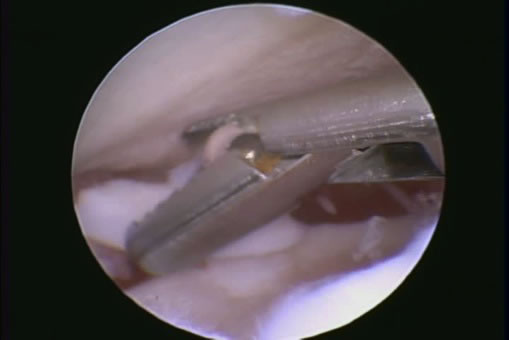

麻酔下整形外科的検査、関節鏡検査

安静や外固定、消炎鎮痛剤など。それでも改善がない場合は関節鏡下で高周波熱発生装置をもちいたシュリンケージ、内側上腕靭帯の再建などをおこないます。

関節鏡検査

関節鏡視下で軟骨フラップを切除します。大型犬の成長期の跛行は消炎鎮痛剤等による対症療法ですませず、跛行原因の早期診断、早期治療が重要です。

内科治療に反応がない場合、確定診断と治療をかねて関節鏡検査をおこないます。治療として関節鏡視下での腱切断術をおこないます。